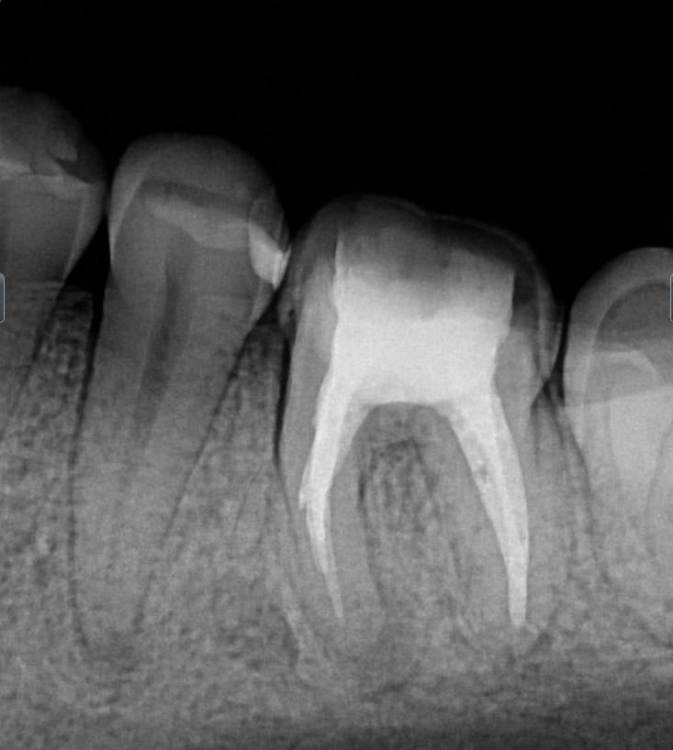

chacraborti Опубликовано 9 декабря, 2023 Поделиться Опубликовано 9 декабря, 2023 Зуб 35 реагирует на температуру, зуб живой . Как один из вариантов решения проблемы предложили поменять пломбу т.к под пломбой на томографии врач увидел темное пятно. Другой врач по рентгену и на осмотре не предлагал мне замену этой пломбы. Подскажите стоит ли менять пломбу в данной ситуации? Не советуйте мне пожалуйста депульпировать зуб, он живой с малой пломбой и мне его жалко, я ищу менее радикальный способ решения вопроса, но бессмысленные действия тоже не хочу совершать. Прилагаю ссылку на томографию и рентгеновский снимок. Томография: https://drive.google.com/file/d/14-hLWeFzCL1Uwm5Rdl3TzB6oF3yacujY/view?usp=sharing Ссылка на комментарий